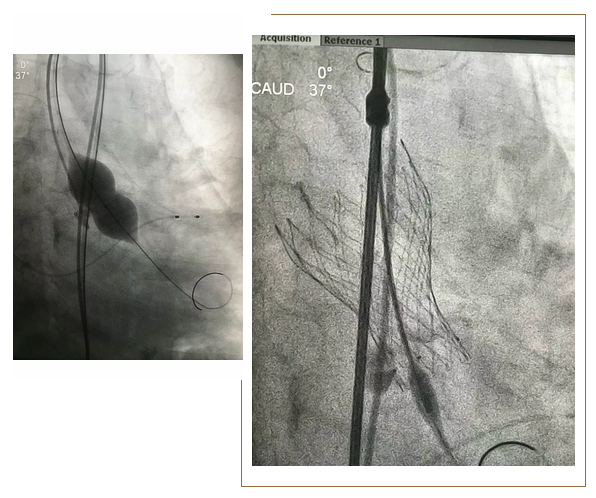

近日,我院心血管内三科郭延松主任医师、陈新敬副主任医师团队顺利为一名92岁超高龄重度主动脉瓣狭窄患者完成经皮导管主动脉瓣植入术,这是目前国内接受经皮导管主动脉瓣植入术的少数超高龄患者之一。

据了解,该患者患有重度主动脉瓣狭窄,合并慢性阻塞性肺疾病、贫血,气促、胸闷多年,近半年症状加重,平卧休息都成了奢望,反复经药物治疗仍无明显效果,心脏超声提示主动脉瓣瓣叶严重钙化毁损,彻底失去正常的开闭功能,已经导致患者心脏泵血严重受阻,随时可能导致晕厥甚至猝死。郭延松主任医师带领的团队联合麻醉科、超声科、放射科、心血管外科、手术室等多学科对手术方案及术后注意事项进行认真比较和讨论后,决定为该患者选择经导管主动脉瓣植入术。手术取得圆满成功,患者术后第5天即顺利出院。

经导管主动瓣植入术是目前国际先进、国内领先的诊疗技术,仅需通过股动脉穿刺将自膨式瓣膜置入主动脉瓣位,替代病变的自身主动脉瓣,恢复其应有的开闭功能。我院自开展经股动脉途径的经导管主动脉瓣植入术以来,已先后成功为多名存在手术禁忌证、高龄等患者完成经皮导管主动脉瓣置换术,受到好评。此次92岁高龄患者手术的成功,标志着我院经皮导管主动脉瓣置换术的多学科协作和手术操作能力日趋成熟。